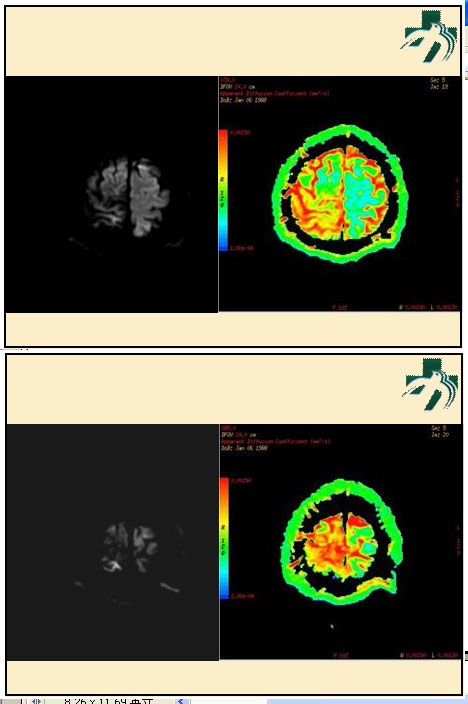

奴卡氏菌感染

第九期三博

读片会

病例之四

北京协和医院 提供

男性,22岁。自觉虫咬后皮疹、肢体麻木4月